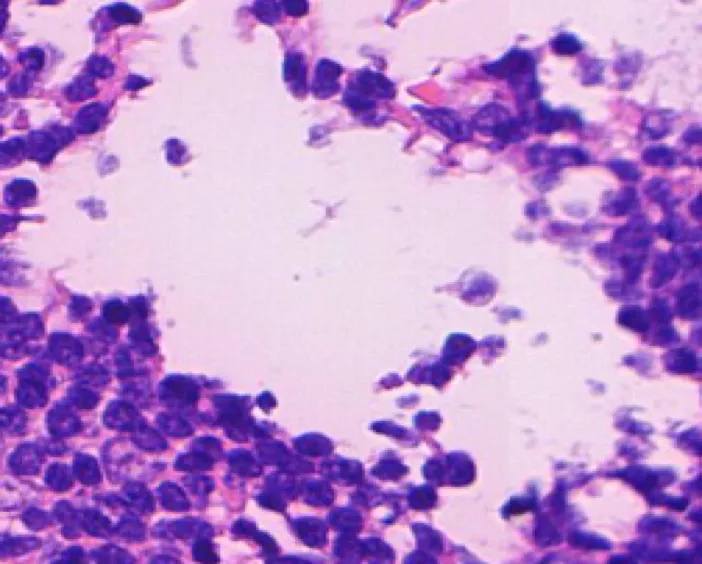

Block interception and precise amplification of gastric biopsy digital images; Tumor segmentation model

and heat map analysis; Feature extraction, negative and positive classification to predict tumor probability with high sensitivity.

1. Identification image: high-quality, direct, accurate, intelligent.

Identification Pattern

1. Normal tissue

2. Low & High grade

intraepithelial neoplasia

3. Adenocarcinoma

4. Signet ring cell carcinoma